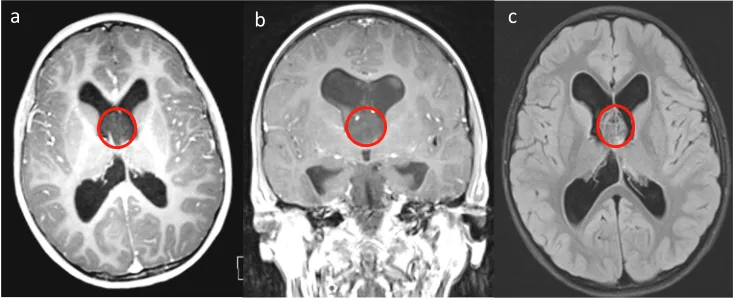

菊形团形成性胶质神经元肿瘤(RGNT)是一种罕见的肿瘤类型,文献报道主要发生在第四脑室区域。该病变被描述为良性肿瘤,通常局限于周围组织结构,包括小脑蚓部、中脑和脑导水管。...